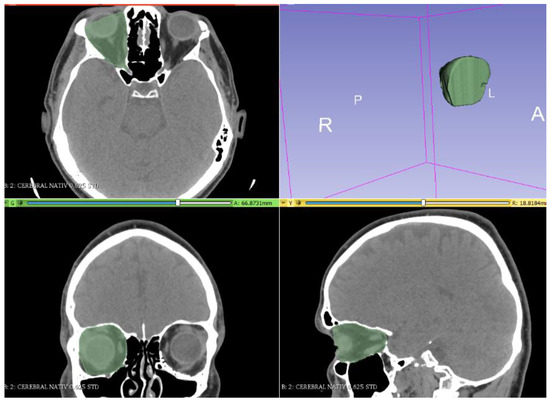

2. Materials and Methods

3. Results